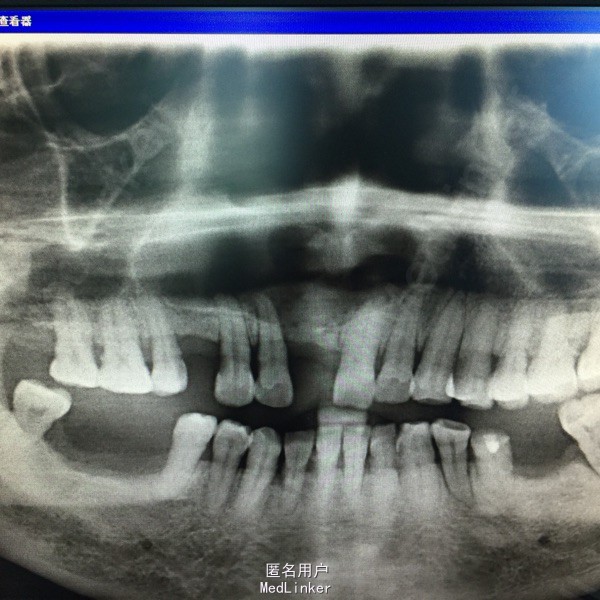

患者上颌前牙区肿胀1年多

查:上前牙区肿胀明显,溢脓,12、13、15、21牙叩(十),11、14牙缺失。全景牙片示:15至21根尖阴影,大小约10x4.5cm,边缘白色阻射线。

上颌骨囊肿 处理:12、13、15、21行根治疗,上颌骨囊肿行开窗减压术,定期复诊。